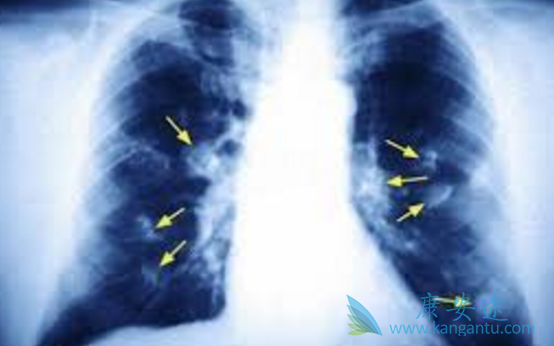

现在大家都谈癌色变,一旦得了癌症就觉得离死不远了。其实,随着检查手段和医疗技术的发展,很多癌症现在都是可以治愈的,就算是一些不能治愈的癌症,也可以通过一系列的治疗实现带瘤生存。以肺癌为例,如果患者能够在早期发现病情,一般手术加上一些辅助治疗就可以完全根除癌细胞,即便是中晚期的患者,如果检测到有明确的治疗靶点,接受相关的靶向治疗,很多病人也能生存很长时间,有的患者生存甚至超过10年。那具体来说肺癌中晚期的治疗方案有哪些?

肺癌治疗主要分为:手术治疗、放射治疗(放疗)、化学治疗(化疗)、靶向治疗、生物免疫治疗。专业的肿瘤内科医师、呼吸内科医师、放疗科医师、胸外科医师会共同商讨,根据每个患者的病情、身体状况、本人的要求等等,为其私人订制一个最合适的治疗方案,临床上称之为「个体化治疗」。例如例如局部晚期(综合淋巴结转移),早发现病情的病人建议手术之后辅助放疗或化疗。